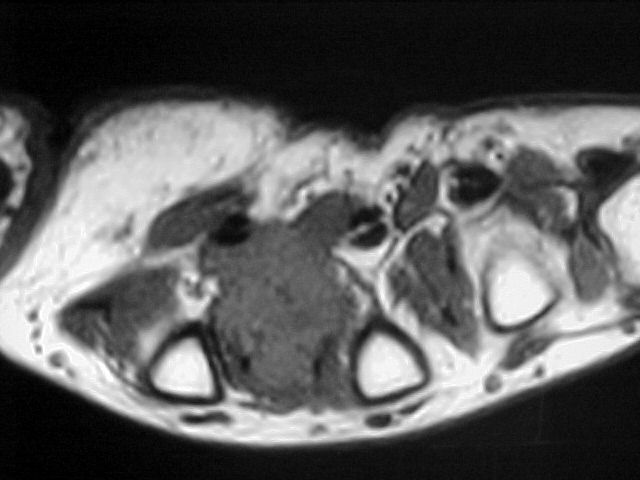

36y, male, Discrete pain and increase of volume between the 2nd and 3rd MCs

Case to follow the sent by Kyung, showing a glomus tumor in an unusual place

Glomus tumors